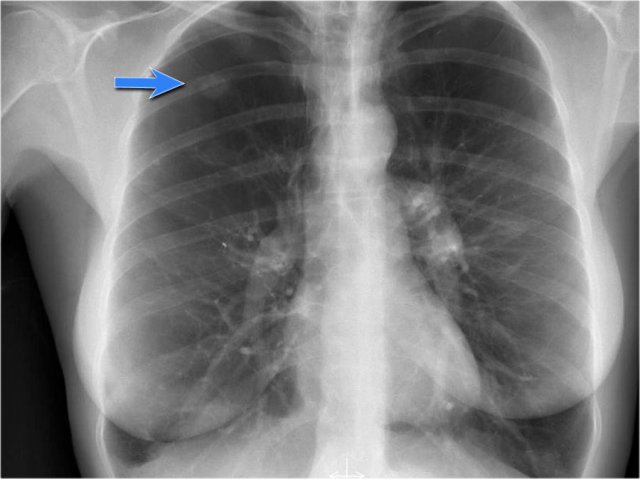

A common normal variant is the azygos lobe.

The azygos lobe is created when a laterally displaced azygos vein makes a deep fissure in the upper part of the lung.

On a chest film it is seen as a fine line that crosses the apex of the right lung.

Here another patient with an azygos lobe.

The azygos vein is seen as a thick structure within the azygos fissure.